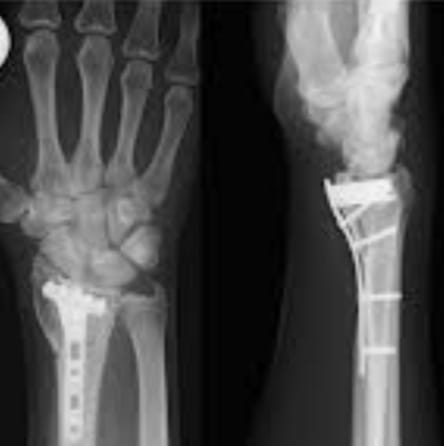

Hospital Gallery